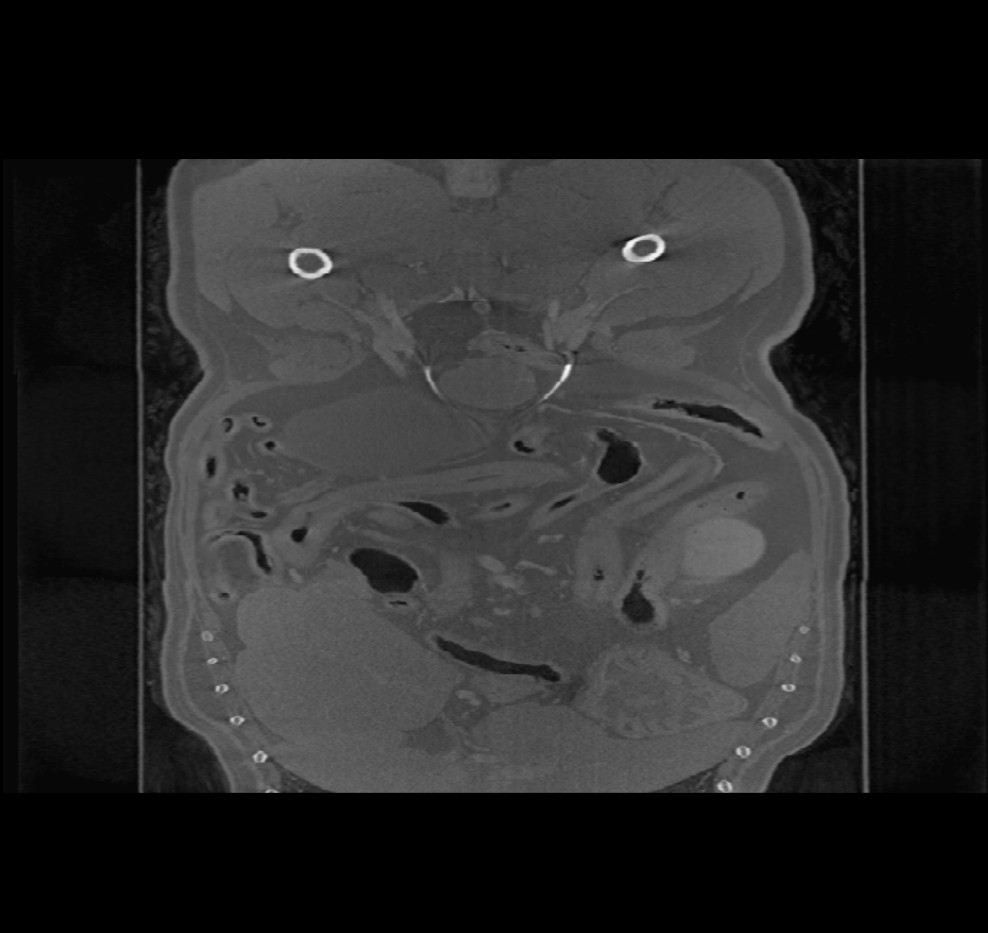

Volumetrikus DICOM képek (CT és MR modalitás) megnyitásakor a Megjelenítő felső eszköztárában egy további menü érhető el (Képsíkok) néven. A kép orientációjának módosításához válassz a három elérhető sík közül: (Axialis, Koronális és Saggitális).

A kiválasztott sík befolyásolja a CT/MR szeletek helyzetét és orientációját, valamint azok 2D síkon történő rekonstrukcióját.